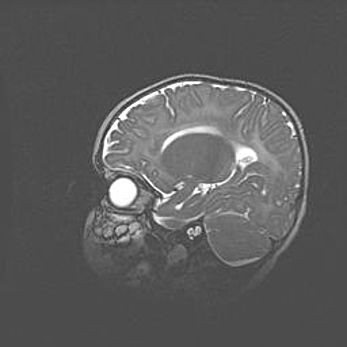

Лейкомаляция с кистозно-глиозной дегенерацией головного мозга.

Возраст: 2 месяца 25 дней

Вес: 6400 г

Окружность головы: 40 см

Срок гестации: 41 неделя

Лейкомаляцию относят к ишемически-гипоксическим повреждениям головного мозга, диагностируемым у новорожденных. При лейкомаляции в головном мозге обнаруживают очаги некроза, возникшие после тяжелой гипоксии и нарушения кровотока. В процессе морфогенеза очаги проходят три стадии: 1) развития некроза, 2) резорбции и 3) формирования глиозного рубца или кисты. Перивентрикулярная лейкомаляция (ПЛ) встречается примерно в 12% случаев среди новорожденных, обычно – у недоношенных детей, причем, частота ее зависит от массы, с которой младенец появился на свет. Наибольшее число малышей страдает лейкомаляцией, если масса при рождении 1500-2500 г.